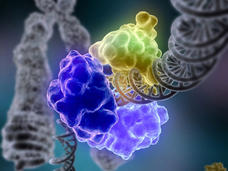

Estudio identifica nuevas oportunidades de inmunoterapia dirigida

Un equipo de investigadores del NCI ha informado que varios tipos de cánceres gastrointestinales tienen mutaciones específicas al tumor que pueden ser reconocidas por el sistema inmunitario, lo que ofrece una posible oportunidad terapéutica para pacientes con estos tumores.